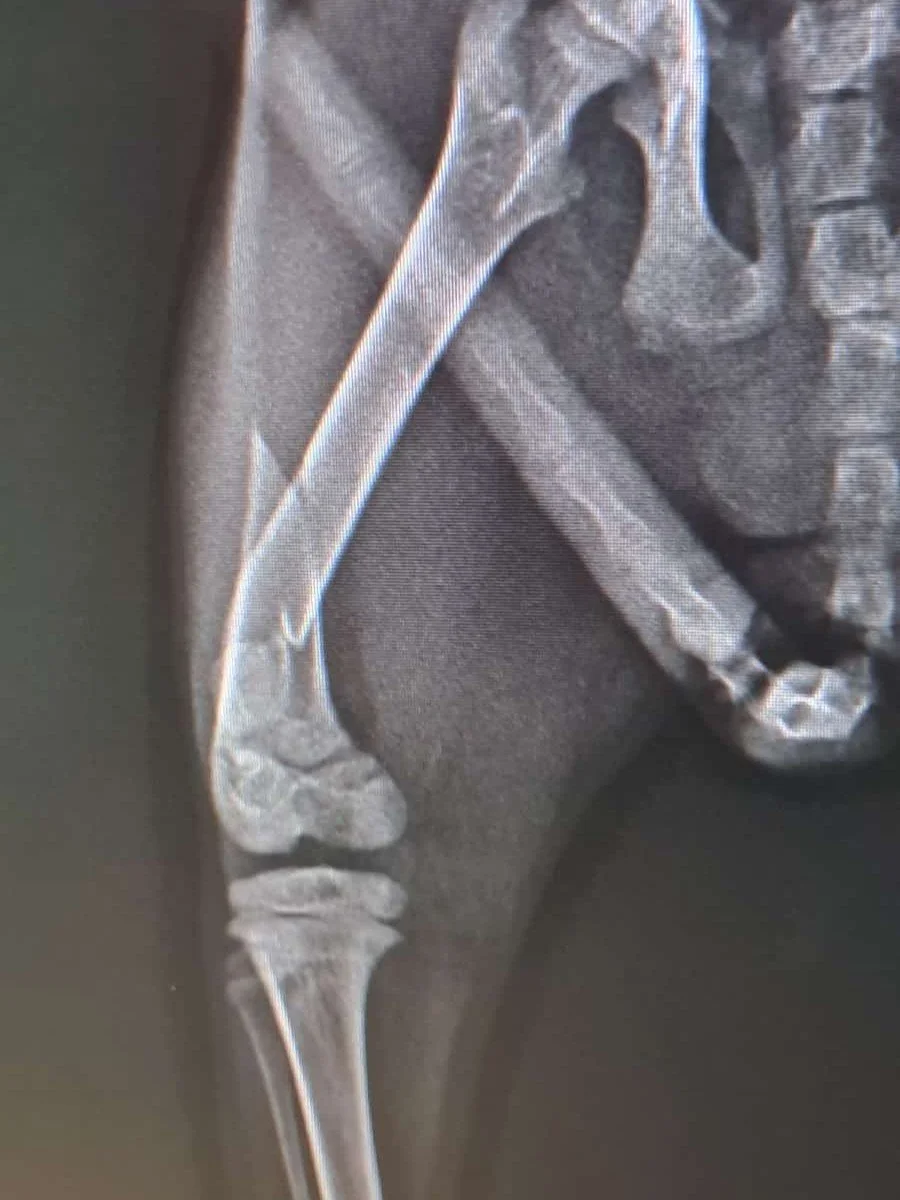

Der kleine Babykater lag halbtot am Strassenrand… angefahren, durchnässt, halb wahnsinnig vor Schmerzen und Angst. Ein Auto nach dem anderen ist am schwerverletzten Findus vorbeigerauscht… liegengelassen wie Müll, um langsam und qualvoll zu sterben. Bis sich jemand des blutigen kleinen Fellknäuels erbarmt hat… ihn halbtot aus dem nassen Dreck gehoben, in eine Decke gewickelt und zum Tierarzt gebracht hat.

Der kleine Findus hatte einen Oberschenkelbruch. Nach wochenlanger Behandlung und einem Verband fast größer als der ganze Kater (Danke Andrea Sedar!!!), liebevoller Pflege und Zeit zum Heilen ist Findus heute ein glücklicher, kleiner Kater, der bereit ist die Welt zu erobern. Und das Allerschönste: bei seiner Retterin hat er ein Zuhause für immer gefunden!